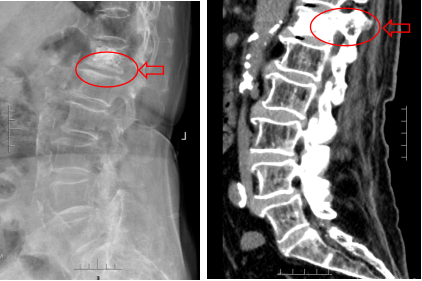

术后影像显示骨水泥分布理想,无渗漏。王奶奶安返病房,术后第一天即可佩戴护具下地活动,患者及家属对疗效非常满意。

术后复查X线 术后复查CT